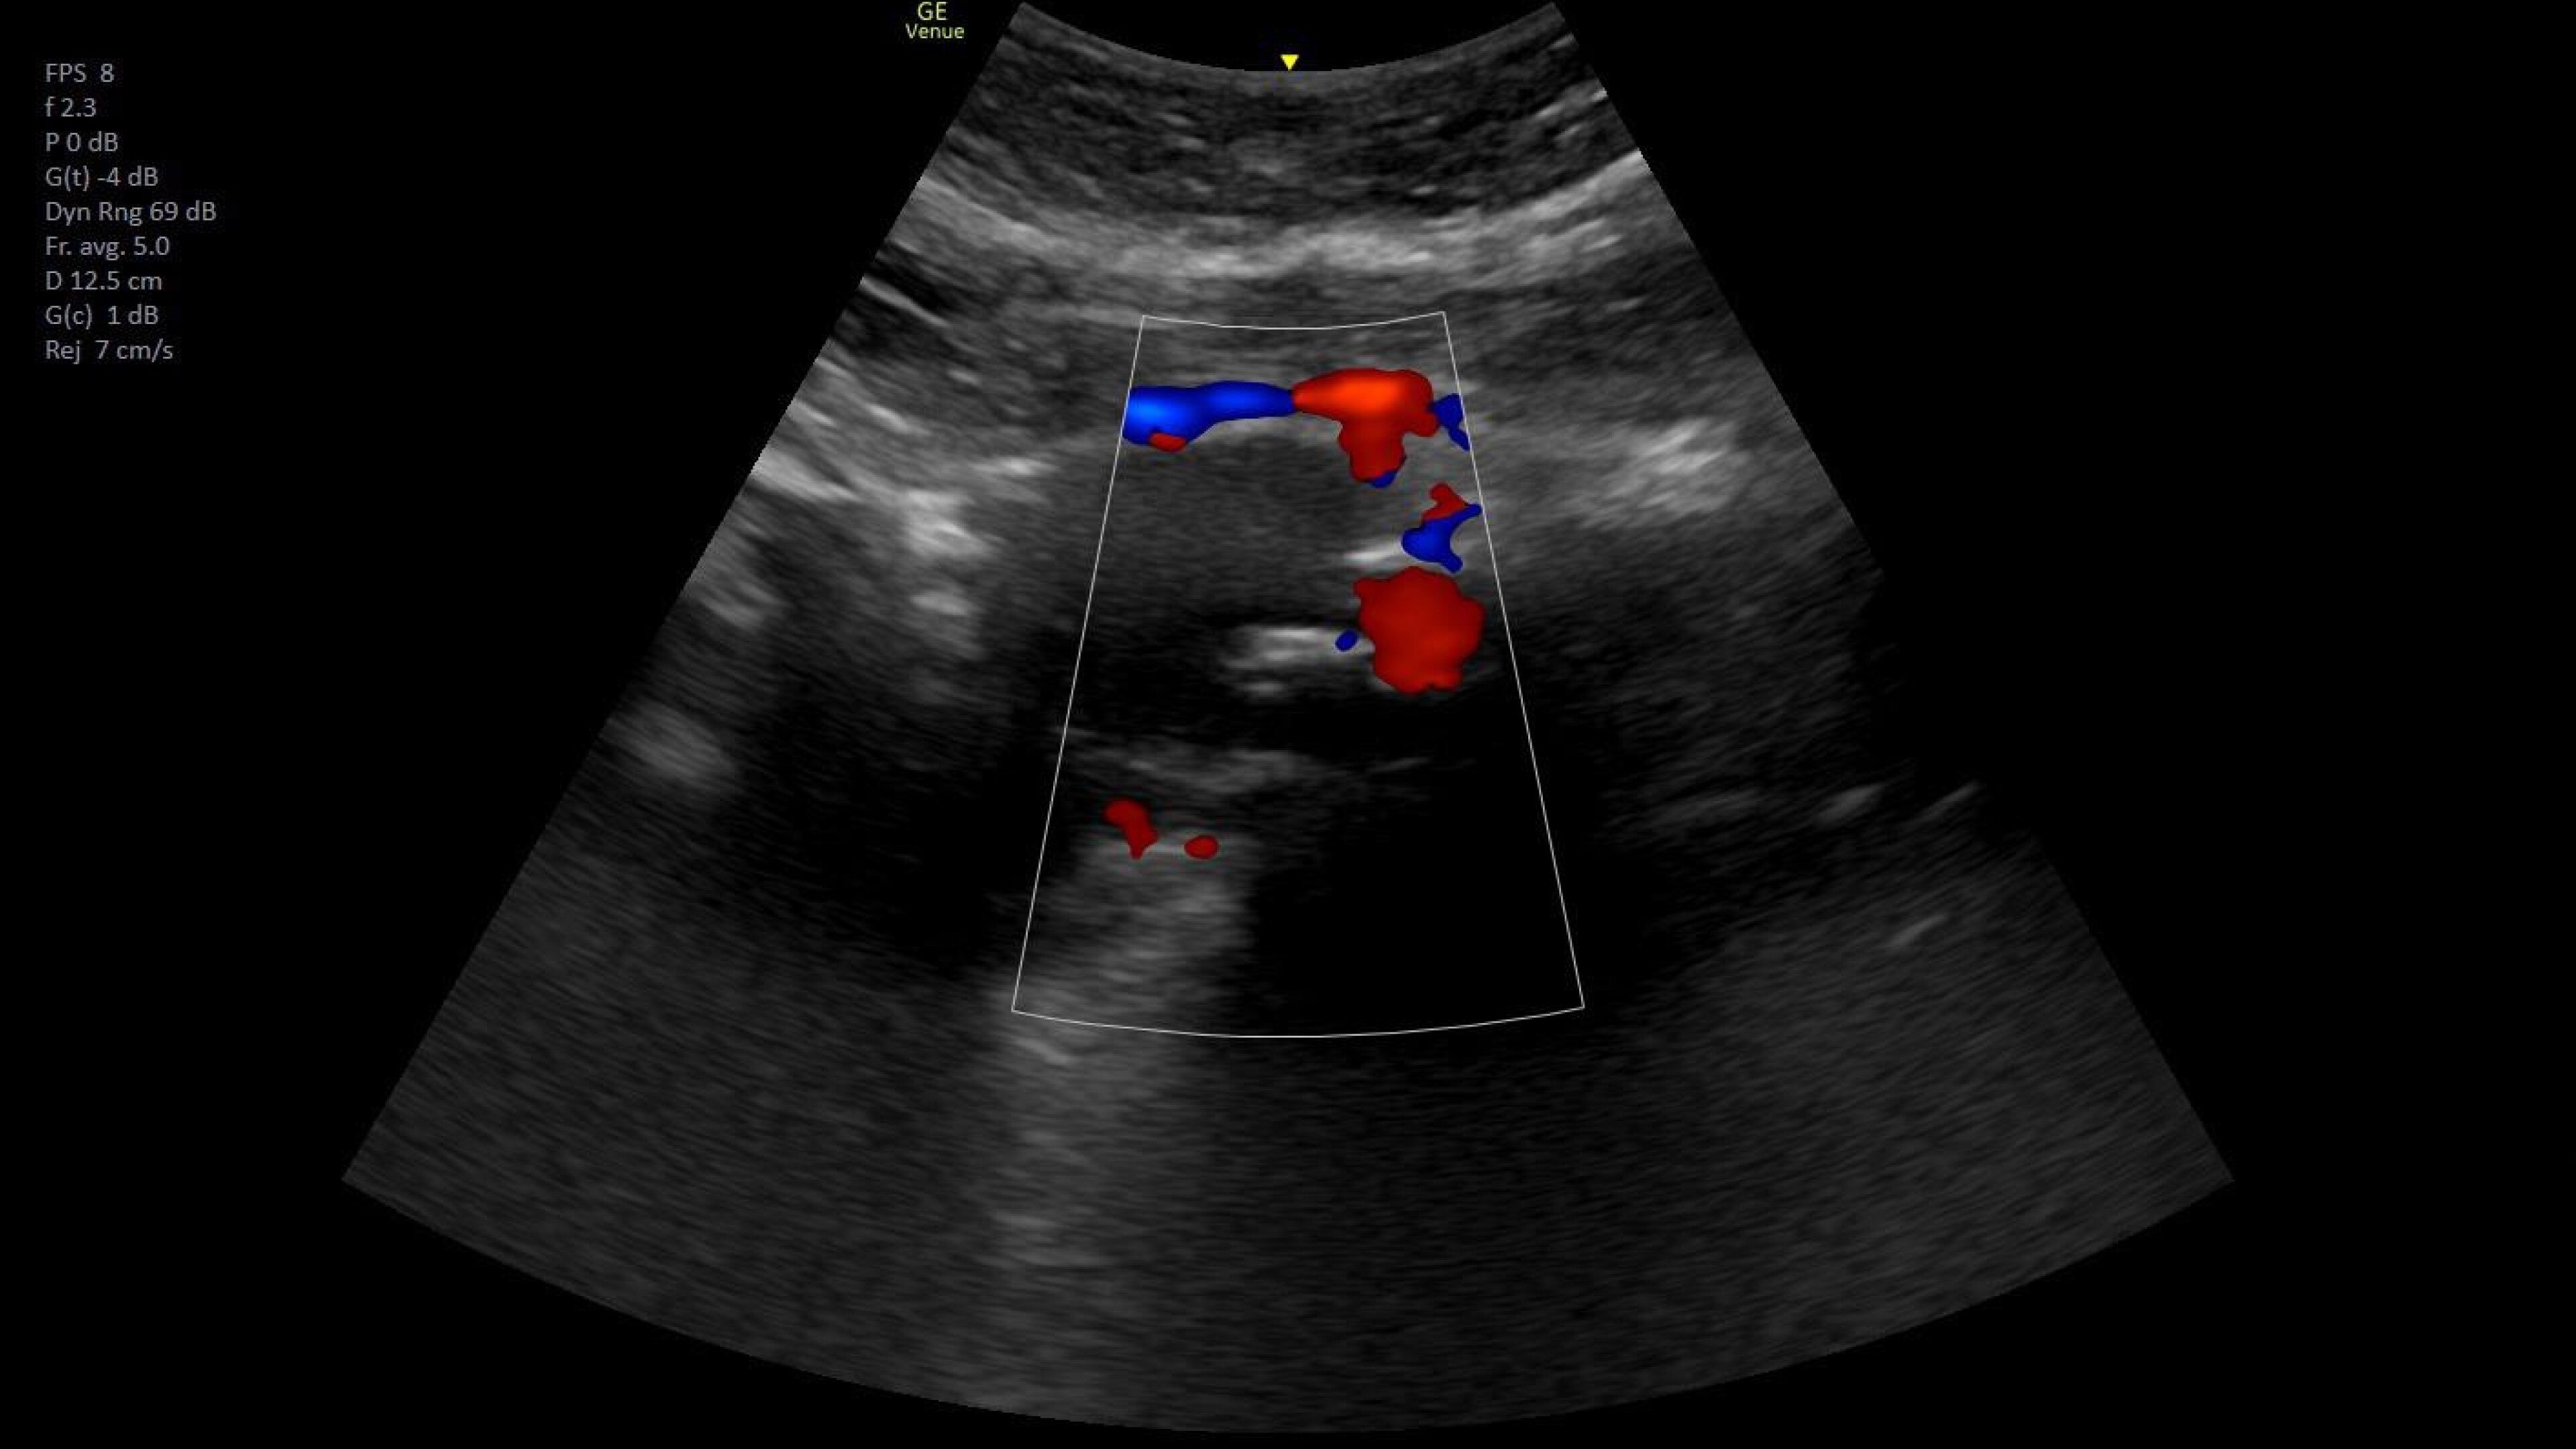

Wireless probe integration

Sync up and go - without wires you’re not tethered to a system or a space

Small yet powerful

Flexible, wireless dual-probes deliver clear images and Venue family software